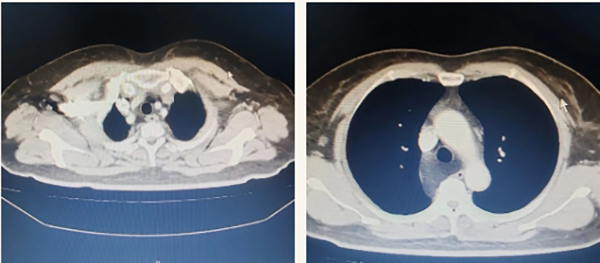

近日,中国医学科学院肿瘤医院山西医院(山西省肿瘤医院)胸外科庄晓飞主任医师团队在科主任廉建红指导下,成功为一名患有复杂后纵隔巨大脂肪瘤的患者实施高难度肿瘤切除术。手术采用“胸腔镜辅助小切口”微创技术,精准剥离与血管神经紧密粘连的12cm×8cm×6cm 肿瘤,实现“零损伤”切除,患者术后一周康复出院,标志着我院胸外科微创技术再攀新高峰。

患者肿瘤位于后纵隔,体积庞大且与周围组织关系复杂:肿瘤完全包裹奇静脉,分离时易引发致命性大出血;与迷走神经形成致密粘连,损伤可能导致心律失常、呼吸困难等严重并发症;长期压迫使食管壁菲薄如纸,术中穿孔风险极高。

面对如此复杂的手术局面,廉建红主任指导手术团队创新性采用 “四步攻坚”策略:术前运用增强CT+MRI三维重建技术构建肿瘤与血管神经的3D立体模型,误差控制在1毫米以内;术中借助胸腔镜10倍放大成像系统实现血管神经的精细分离,采用4cm小切口辅助离断奇静脉,减少了手术创伤;术前,手术团队独创了“食管支撑术”,预置胃管强化食管支撑;术中实施“食管壁零损伤剥离术”。手术过程中,团队借鉴食管癌手术经验,成功保全迷走神经肺支,避免了术后呼吸功能障碍。庄晓飞主任医师表示:“此类手术如同在精密机械中操作,需要毫米级精度与多学科协作的完美结合。”